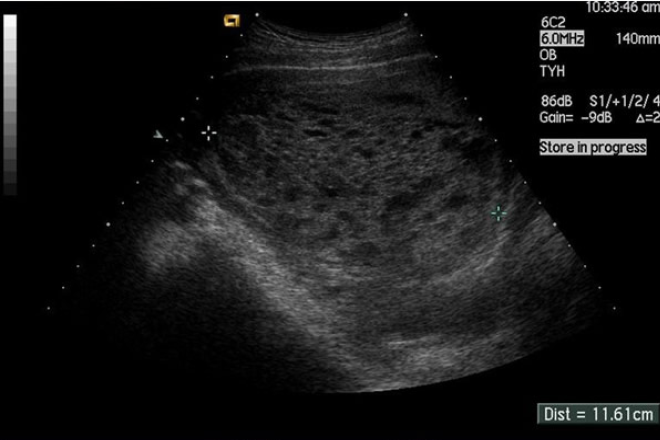

DBP: 78 mm, fémur 61mm, latidos cardiacos (LC) presentes, se observan movimientos corporales. Placenta con imagen mixta en panal de abeja, característica de una mola parcial. Índice de líquido amniótico (ILA) 9 mm.

En discusión colegiada en el servicio de Obstetricia se decide terminar el embarazo por cesárea con el diagnóstico de mola parcial con feto vivo. Riesgo alto de hemorragia obstétrica.

El recién nacido tuvo un peso de 1 266 gramos, Apgar 9-9. Líquido amniótico meconial fluido. Placenta voluminosa, con ramilletes vesiculares, peso de 2 600gramos. El estudio anatomopatológico confirmó el diagnóstico.

Se presenta el caso de una mola hidatiforme parcial con feto vivo en el 3er trimestre del embarazo. El diagnóstico no se realizó inicialmente. La confirmación por ultrasonografía fue en la semana 32 de la gestación.